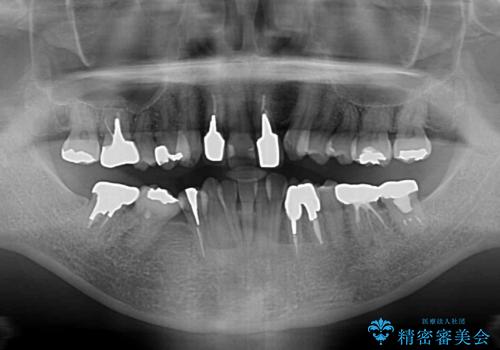

- 非対称な前歯や奥歯の目立つ銀歯を気にして来院された患者様です。

左上前から2番目の歯は、以前裏側に位置していたことから抜歯をされていましたが、前歯の非対称が長年気になっているとのことでした。

矯正治療によって前歯にスペースを作り、左右対称となるようにオールセラミッククラウンにて補綴治療を行うとしました。

他にも奥歯の咬み合わせに問題があったので、全顎的な矯正治療を行い、前歯以外にも口を開けたときに目立つ奥の銀歯をセラミッククラウンにて補綴治療を行うこととしました。